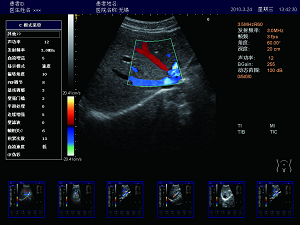

精確血流成像

智能識別血流運動和組織運動,使血流更充盈,組

織邊界更清晰。

肝臟 脾臟 多普勒血流

高效的多譜勒技術

多普勒幀相關 血流圖像更平滑更清晰。

多普勒快速優化 對于危重病人,兒童可以在短時間內獲得最佳的血流成像。

壁濾波器 增強血流邊緣清晰度,產生精準的發射波形,達到最佳匹配效果,提高全聲場的回波質量。